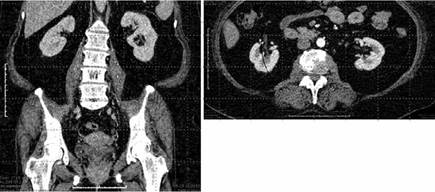

FIGURA 4: TAC contrastada en fase nefrográfica corte coronal a la izquierda y axial a la derecha, ambos riñones en situación habitual, ta,año conservado, de contornos lobulados, con adecuado y simetrico nefrograma, sin tumoración, ni cambios inflamatorios

FIGURA 4: